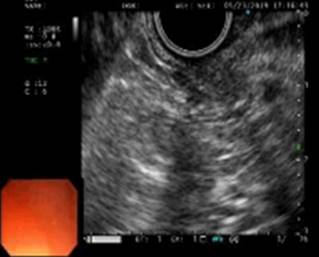

Se presenta el caso de un hombre de 54 años procedente del área rural de Socorro, Santander, a quien se le realizó una endoscopia digestiva alta para la evaluación por un posible cuerpo extraño esofágico, y se encontró como hallazgo incidental la presencia de una lesión de 8 mm en el antro hacia la curva mayor de 8 mm de diámetro, altamente compatible con una neoplasia gástrica temprana 0-Is (Figura 1). Las biopsias fueron compatibles con adenocarcinoma bien diferenciado. Con dichos hallazgos consultó al Hospital Regional Manuela Beltrán, donde se complementaron los estudios con una ultrasonografía endoscópica gástrica, que evidenció el compromiso de las capas ultrasonográficas I y II (hasta la muscular de la mucosa) (Figura 2); por tanto, se clasificó como uT1uN0, compatible con un cáncer gástrico temprano. Como estudios adicionales, una tomografía axial computarizada (TAC) de abdomen contrastada descartó la presencia de metástasis a distancia o compromiso ganglionar. Se programó para realizarle una mucosectomía endoscópica gástrica.